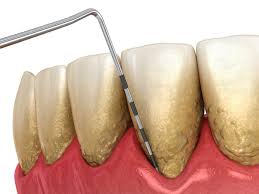

• Scaling and Root Planing (Deep Cleaning) – Thorough cleaning below the gumline to remove plaque and tartar buildup.

• Bleeding or swollen gums

• Tooth sensitivity near the gumline